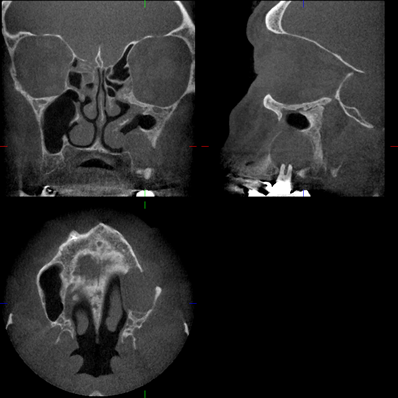

Bilder NNH

Kuhn'sche Zelle Mukozele SH Knochenneubildung Stirnhöhle sagittal Concha bullosa radikuläre Zyste